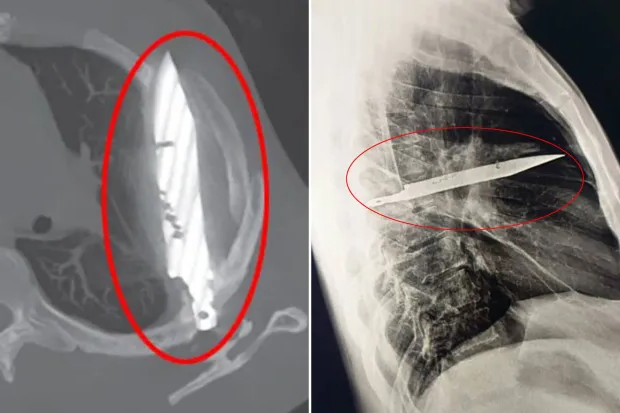

«Первоначальная визуализация с помощью боковой рентгенограммы грудной клетки выявила застрявший металлический предмет в средней части грудной клетки, а окружающее затемнение, вероятно, представляет собой рассасывающуюся или хроническую осумкованную гематому или посттравматический фиброз — последствие ножевого ранения пациента», — написали врачи в своем исследовании случая .

Каким-то чудом лезвие ножа, вошедшее через правую лопатку, не затронуло жизненно важные органы. Во время ссоры с мужчиной восемь лет назад в больнице, где он проходил лечение, не было возможности провести рентгенологическое исследование, и, поскольку он не жаловался на боль после заживления ран, никто не стал проводить дальнейшее обследование. Ещё более странно то, что нож так долго не причинял 44-летнему пациенту никакого дискомфорта. Гной образовался из-за омертвевших тканей, скопившихся вокруг инородного тела.